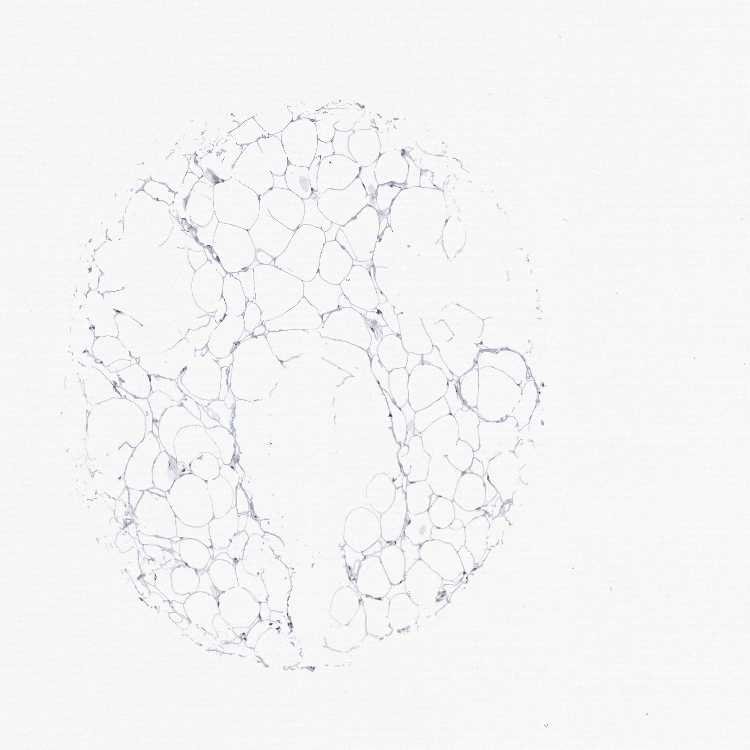

SOFT TISSUE 1 - Antibody stainingi

Antibody staining in the annotated cell types in the current human tissue is reported as not detected, low, medium, or high, based on conventional immunohistochemistry profiling in selected tissues. This score is based on the combination of the staining intensity and fraction of stained cells.

Each image is clickable and will lead to virtual microscopy that enables deeper exploration of all samples and also displays staining intensity scores, fraction scores and subcellular localization as well as patient and tissue information for each sample.

SOFT TISSUE 2 - Antibody stainingi